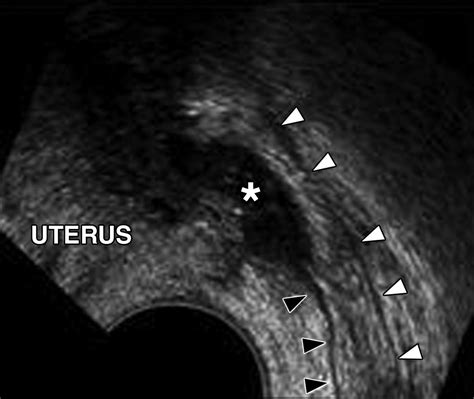

• posterior cul de sac ultrasound

• posterior cul de sac endometriosis

• posterior cul de sac fluid

• posterior cul de sac radiology